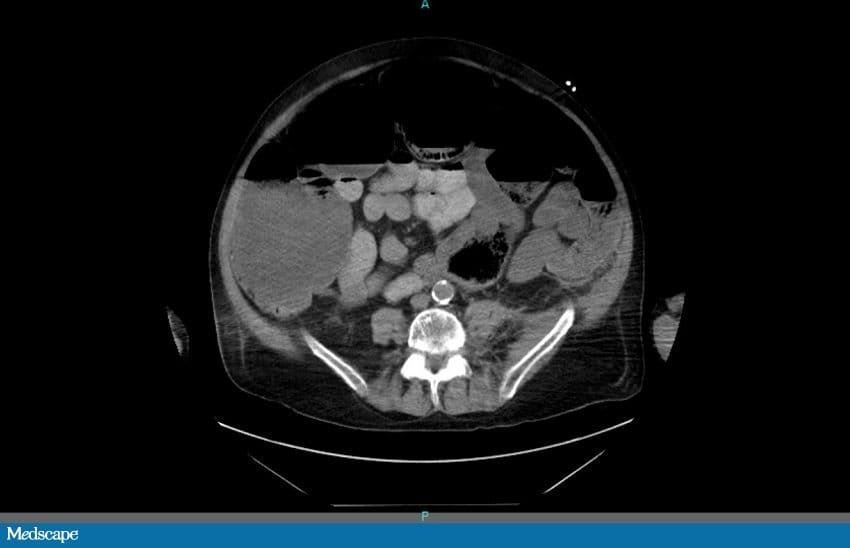

Todos os outros exames laboratoriais estão normais. É feita uma radiografia de abdome. O paciente é internado por causa dos seus exames. Uma tomografia computadorizada (TC) de abdome e pelve sem contraste é feita na sequência. Os achados dos exames de imagem são mostrados abaixo (Figuras 1 a 4).